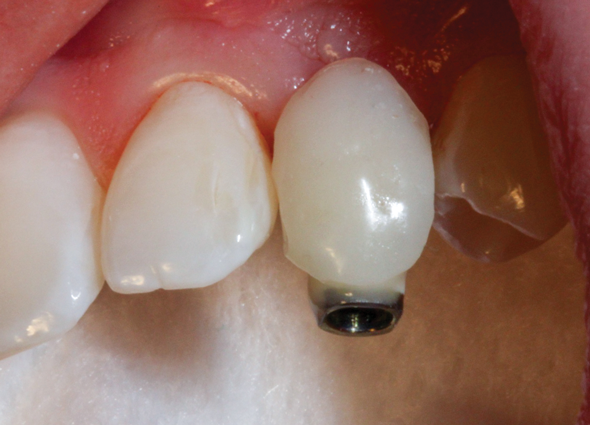

(36.) The implant’s primary stability was assessed by RFA, and the ISQ value greater than 65 was used to determine that immediate provisionalization was indicated.

Figure 36

(37.) The implant’s primary stability was assessed by RFA, and the ISQ value greater than 65 was used to determine that immediate provisionalization was indicated.

Figure 37